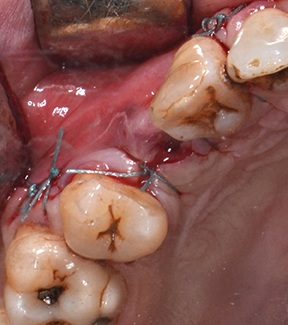

A full-thickness trapezoidal flap was elevated to expose the recipient site (Fig. 4). After releasing all muscular attachments, flap extension was checked coronally (Fig. 5).

Fig. 4: Intraoral view of the atrophic bone area

Fig. 5: Extent of flap release